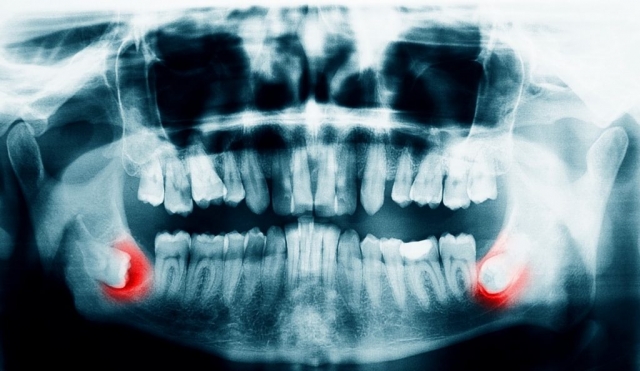

Wisdom teeth, also known as third molars, often emerge in late adolescence or early adulthood. However, there is often insufficient space in the mouth to accommodate these teeth properly. As a result, they may become impacted, meaning they fail to fully emerge or grow in at an angle. Impacted wisdom teeth can lead to pain, infection, swelling, and damage to surrounding teeth. In such cases, surgical extraction is necessary to prevent further complications.